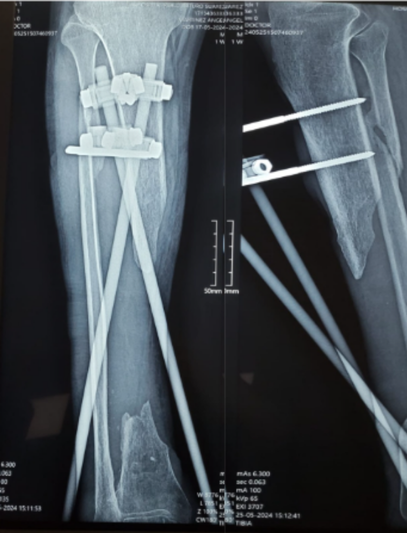

Tras un accidente de tránsito, Yessenia presentó una fractura expuesta con un defecto óseo de 10 cm en su pierna. Había recibido tratamientos previos sin éxito y su movilidad estaba en riesgo.

Con la técnica de osteogénesis por distracción y el uso de un tutor circular Ilizarov, se inició un proceso de regeneración ósea progresiva, acompañado de un seguimiento cercano.

Hoy Yessenia evoluciona favorablemente, conserva movilidad en su rodilla y tobillo, y está recuperando la independencia que pensaba perdida.